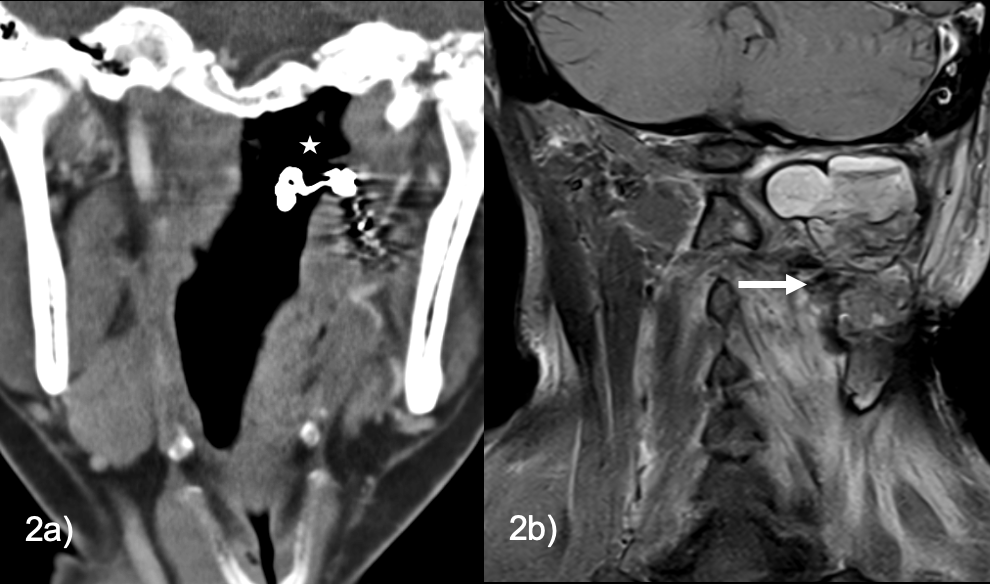

• Using OPTIMISE data, we compared men and women with regards to baseline characteristics, functional outcomes and, as our primary outcomes, procedural complications and sICH

• sICH was defined  as a ≥4-point increase in the NIHSS score associated with the presence of parenchymal hematoma type 1 or 2 on follow-up CT, as determined by the treating physician

Results

3631 patients were included for analysis:

• Women were older (71.8±14.6 vs 68.0±13.1 years, p<0.001).

• There were no differences in median time from onset to puncture {232 (155-365) men vs. 235 (163-377) women, p=0.159}, and from puncture to reperfusion between sexes {(25 (17-37) vs. 24 (17-37), p=0.984}.

•  There were no differences in sICH rates {44 (2.5%) vs. 37 (2%), p=0.388}.

• Procedural complication rates were not different between men and women (5.8 vs 5.6% p=0.76)

Table: Baseline characteristics in male and female

Bleeding complications in ischemic stroke3 e1619443612145

Conclusion

• There were similarly low and reassuring rates of sICH and procedural complications between men and women undergoing EVT in this large multicentre prospective cohort.